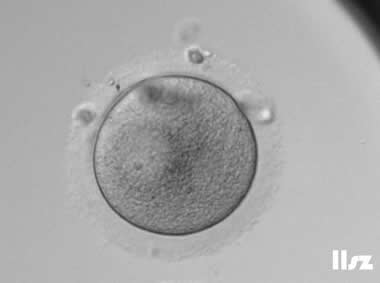

3. 成熟卵母细胞(MII)及其COCs(正常COCs)

卵细胞呈现规则的圆形且颜色较浅,放射冠完全分散,颗粒细胞团较大,排列稀疏。成熟卵母细胞一般在取卵后体外培养2-6小时再行授精。

|  |

| 0小时COCs的MII卵(4x) | 0小时COCs的MII卵(10x) |

|  |

| 2小时COCs的MII卵(10x) | 4小时去颗粒细胞后的MII卵(10x) |